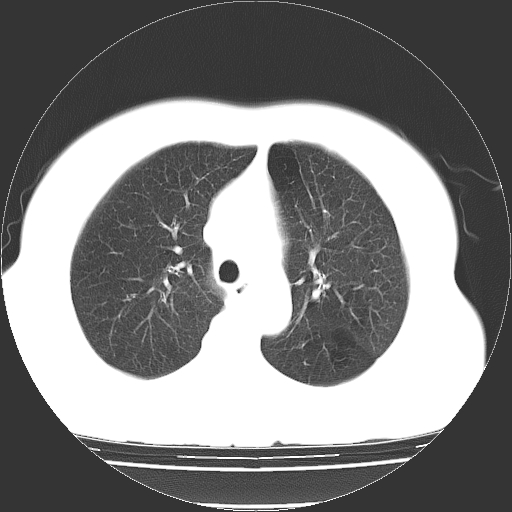

标题: CT13141:女,70岁,咳嗽、胸闷半个月。 [打印本页]

标题: CT13141:女,70岁,咳嗽、胸闷半个月。

女,70岁,咳嗽、胸闷半个月。纵隔窗未见异常,未上传。

肺大疱的壁甚薄,由肺泡的扁平上皮细胞组成,也可能仅为纤维性膜。可与多种肺气肿并存,常见于间隔旁侧或细叶旁肺气肿,可伴有碳末沉着,如煤矿工人尘肺,或不伴有碳末沉着,如瘢痕组织肺气肿。根据病理形态将肺大疱分为三种类型。

ⅰ型:狭颈肺大疱。突出于肺表面,并有一狭带与肺相连。因为支气管瘢痕组织形成的活瓣性阻塞,肺大疱体积增大系由于肺泡侧支通气和气体滞留。ⅰ型肺大疱壁薄,常由胸膜和结缔组织形成,多发生于中叶或舌叶,也常见于肺上叶,可能由于该部位胸腔负压大,常规胸片即可发现肺大疱的存在。

ⅱ型:宽基底部表浅肺大疱。位于肺表层,在脏层胸膜与气肿性肺组织之间。肺大疱腔内可见结缔组织间隔,但它不构成肺大疱的壁,可见于肺的任何部位。

ⅲ型:宽基底部深位肺大疱。结构与ⅱ型相似,但部位较深,周围均为气肿性肺组织,肺大疱可伸展至肺门,可见于任何肺叶。

当肺大疱体积增大时,周围肺组织受压迫并引起肺脏移位。受压肺组织在x线胸片上,表现为肺大疱周围密度增高阴影。以上三型均见于慢性支气管炎。小叶中心型肺气肿不并发肺大疱。下叶肺大疱常见于有并发症的煤矿工人尘肺和融合性矽肺。